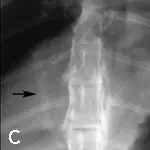

Right lateral (A) and dorsoventral (B) thoracic radiographs were taken. Notice the enlarged pulmonary artery (C, arrow) in the dorsoventral view, which provided a clue to her diagnosis.